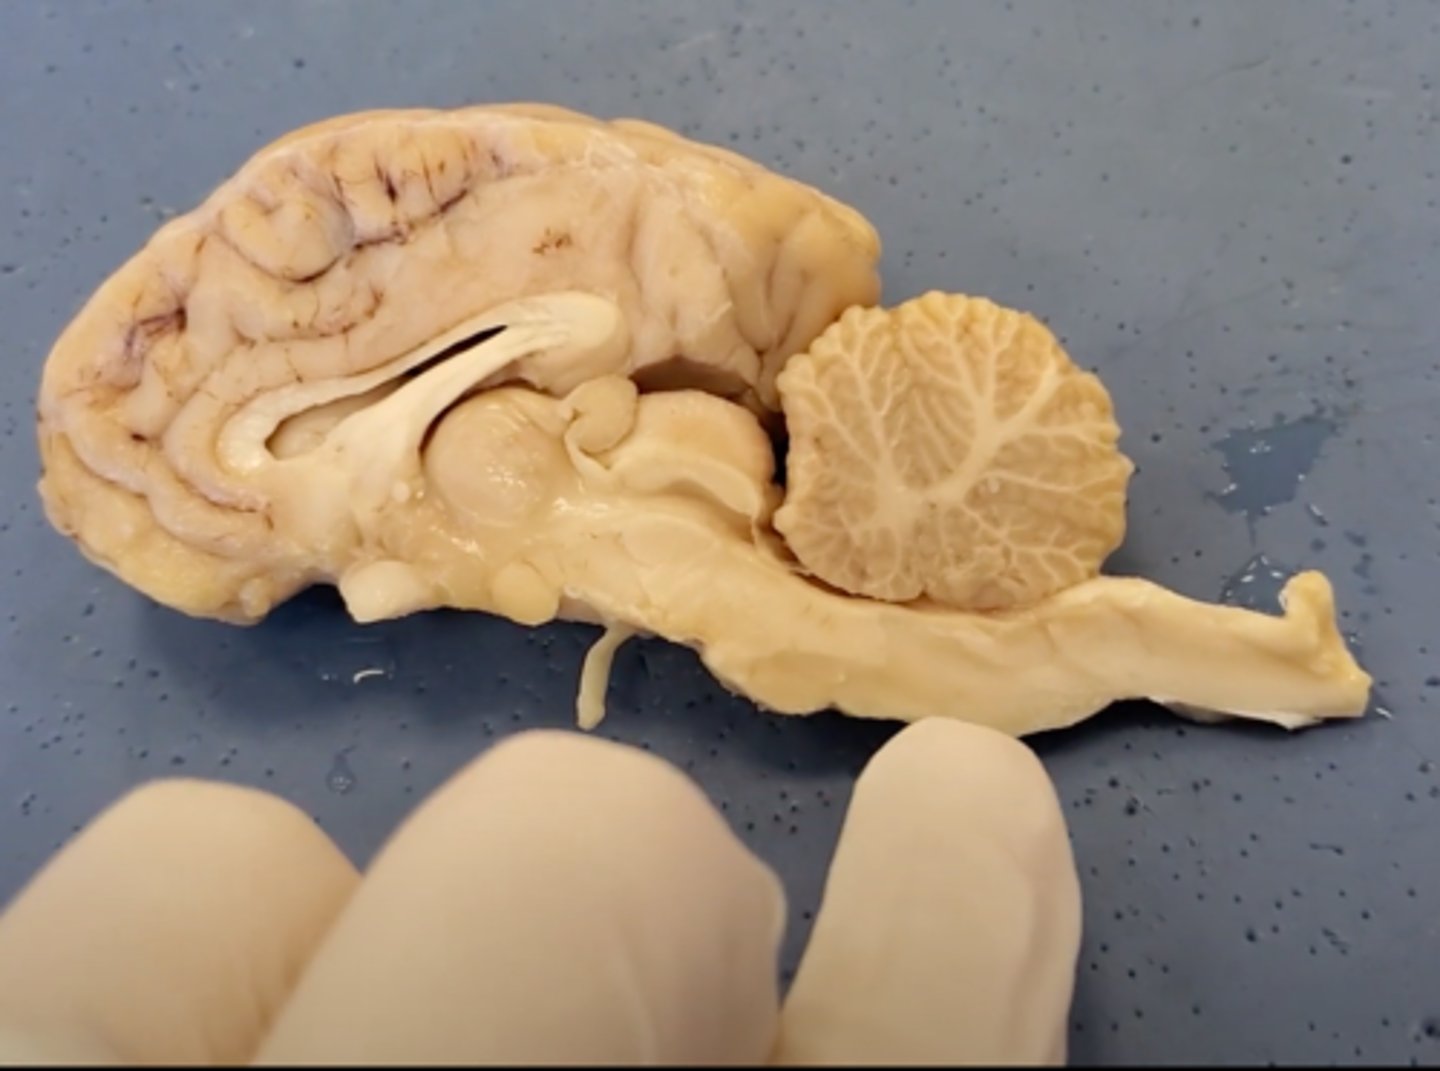

Central Nervous System (CNS)

brain and spinal cord, receives information from sensory receptors, coordinates and integrates the information, and initiates and transmits a response

peripheral nervous system (PNS)

nerves and ganglia, afferent (sensory) nerves channel impulses from sensory receptors to the CNS, and efferent (motor) nerves, which transmit impulses from the CNS to effector organs such as neurons, muscles, and glands.

cerebrum

Area of the brain responsible for all voluntary activities of the body

cerebellum

A large structure of the hindbrain that controls fine motor skills.

olfactory bulb

a brain structure located above the nasal cavity beneath the frontal lobes

medula oblongata

part of the brain that controls breathing, heartbeat, and the size of blood vessels

optic chiasma

the crossing of the optic nerves from the two eyes at the base of the brain

optic nerve

the nerve that carries neural impulses from the eye to the brain

corpus callosum

the large band of neural fibers connecting the two brain hemispheres and carrying messages between them